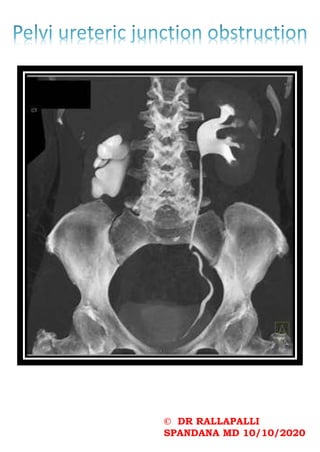

Radiographic features

Imaging findings are many and varied:

•osteopenia: (often seen early) thinning of cortices

and trabeculae

•salt and pepper skull

•demineralisation: usually subperiosteal, however, it

may also involve joint margins, endosteal, subchondral,

subligamentous areas, cortical bone, or trabeculae

•subperiosteal resorption: characteristic subperiosteal

resorption may be seen on radial aspects of middle

phalanges of index and long fingers

•bone sclerosis

• diffuse bony sclerosis

• rugger jersey spine: sclerosis of the vertebral

body endplates

•soft tissue calcification

•amyloid deposition: erosion in and around joint

•insufficiency fractures

•Looser zone

•brown tumours